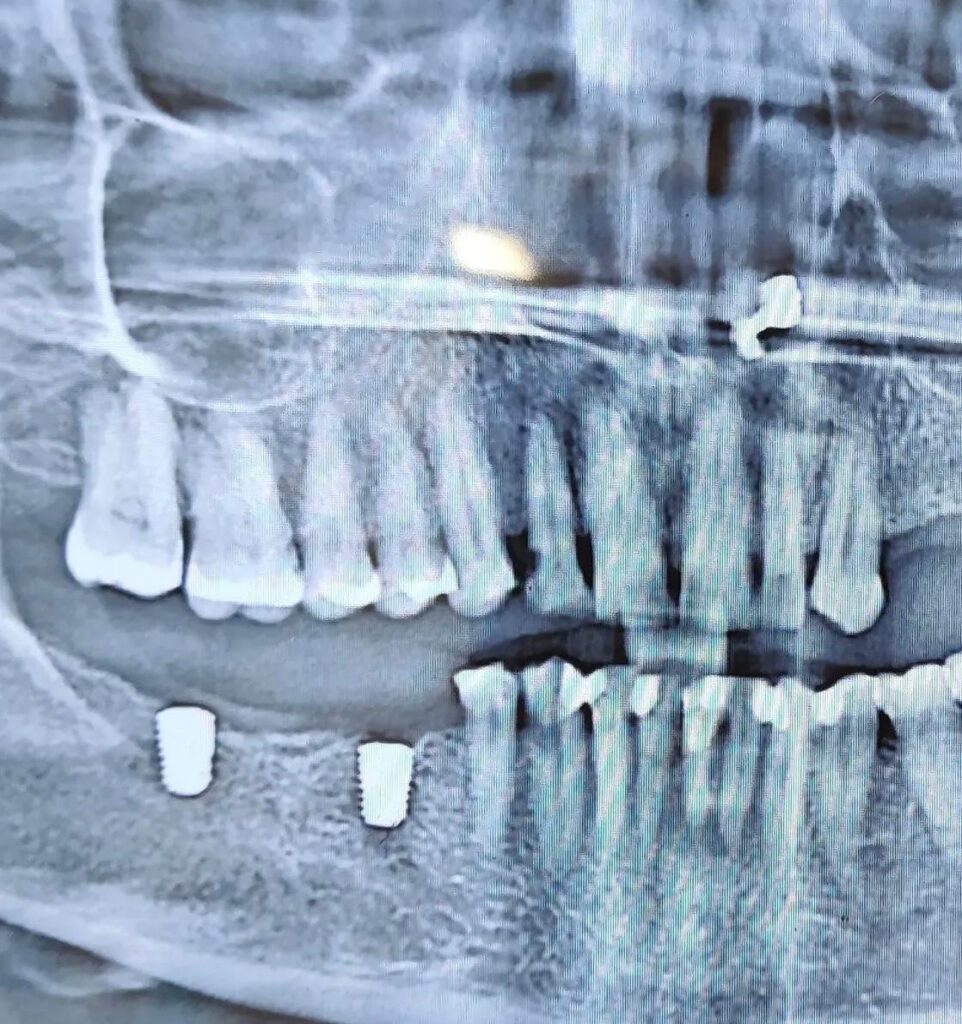

Dental implants are permanent solutions for missing teeth, where titanium posts are placed into the jawbone to support artificial teeth. Full mouth implants replace all missing teeth, restoring complete function, aesthetics, and confidence with natural-looking results.

At Dr Patil’s Elite Smile, we provide advanced dental implants in Wakad Pune using modern technology and precision techniques. Our implants offer long-lasting durability, improved chewing ability, and a natural appearance.

Full mouth implants are ideal for patients with multiple missing teeth, providing a fixed, stable, and comfortable solution compared to traditional dentures.